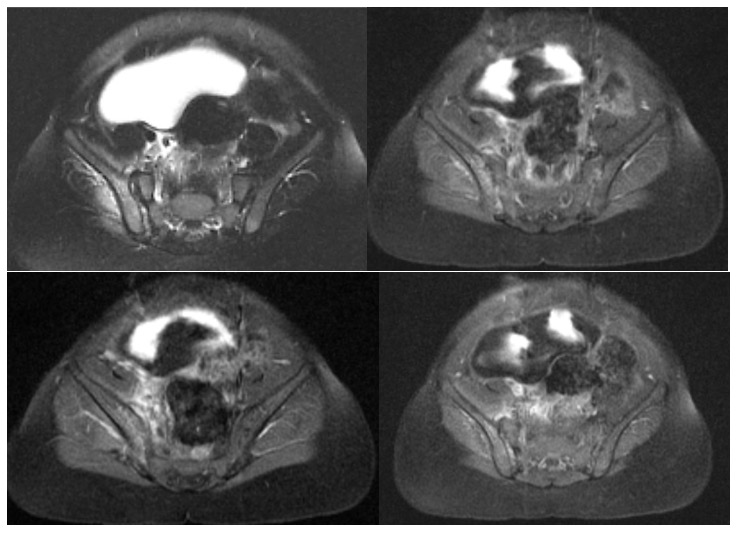

On day 2, magnetic resonance imaging (MRI) showed marrow signal changes with enhancement in the right iliac wing, consistent with acute osteomyelitis, and signs of inflammation in the adjacent muscle (Figures).

Bone infection caused by S pneumoniae is rare, accounting for only 1.3% of acute osteomyelitis cases in children.2 The most common sites of osteomyelitis in children are metaphyses of long bones, most commonly of the femur, tibia, and humerus. Osteomyelitis of the pelvic bones accounts for less than 15% of all cases.3 Pelvic osteomyelitis is associated with substantial soft-tissue inflammation, particularly pyomyositis, in 85% of cases and abscesses in approximately half of cases.4 Our patient had a rare case of pelvic osteomyelitis associated with pyomyositis caused by non-PCV13 S pneumoniae serotype 10A in a vaccinated child.

Pelvic osteomyelitis and pelvic pyomyositis are difficult to diagnose clinically because of their vague presentation mimicking disease of adjacent structures, such as osteoarthritic infection of the hip.5-9 In our case, the patient presented with fever and refusal to bear weight on one lower extremity, in association with leukocytosis and elevated CRP, which raised suspicion for femoral osteomyelitis or septic arthritis of the hip. However, the patient had full range of motion in the right hip, point tenderness on palpation was not elicited anywhere, and radiographic findings of the right hip were normal. This prompted a widening of the differential diagnosis to include infection in the pelvis. Therefore, further diagnostic evaluation was employed using MRI, the most sensitive imaging modality for detecting disease in the bone and adjacent tissues.9,10